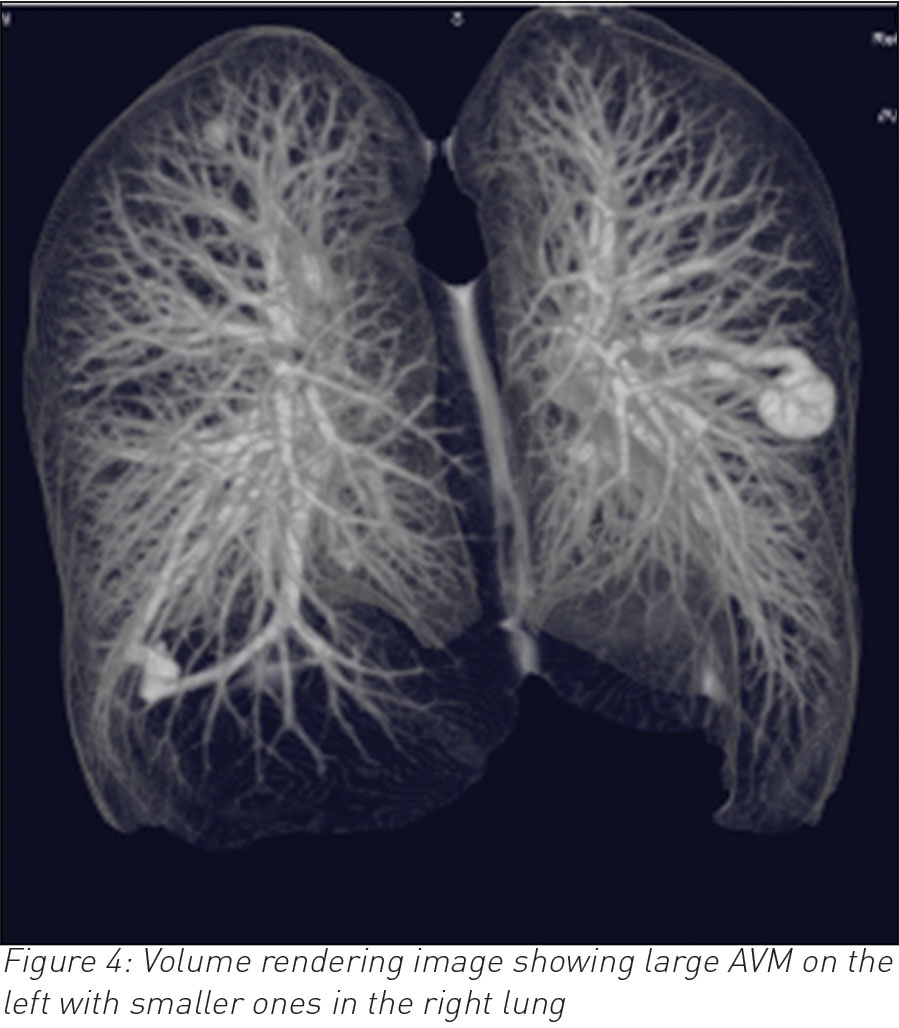

A 35-year-old male, who is otherwise fit and healthy, presented with a 10-day history of cough and temperature. Bloods showed raised white cell count otherwise normal. Chest infection was suspected and a chest radiograph was requested. The latter showed a well-rounded soft tissue opacity in the left midzone with possibly a connecting vessel radiating to the hilum. Two smaller opacities were identified in the right lung. A computed tomography (CT) pulmonary angiogram with intravenous contrast followed and that confirmed the diagnosis of a PAVM of 2cm in the left upper lobe and exquisitely demonstrated the feeding artery and vein with further smaller PVMs of 1cm in the right lung. The patient declined any further intervention.

CT is often the diagnostic modality of choice.3 It differentiates PAVMs from other causes of pulmonary nodules or masses. On CT, the characteristic presentation of a PAVM is a homogenous non-calcified nodule up to several centimetres in diameter or a serpiginous mass connected with blood vessels. Occasionally associated phleboliths may be seen as calcification. Contrast injection shows enhancement of the feeding artery, aneurysmal part and the draining vein.3